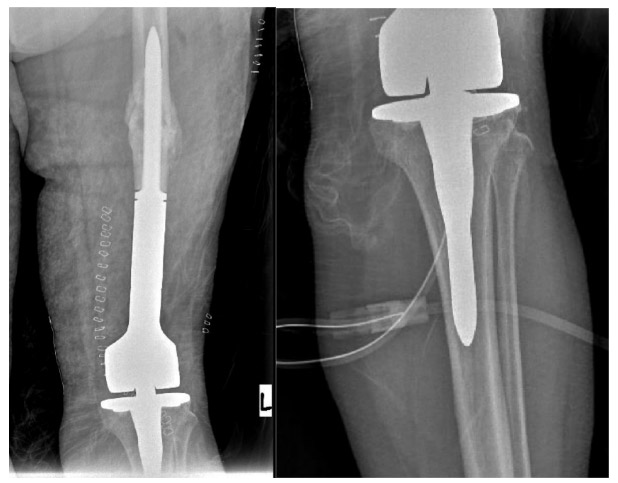

Post-surgery: The X-ray shows the placement of a distal femur tumor prosthesis after the nail inside the bone and the tumorous portion at the lower end of the bone were removed.